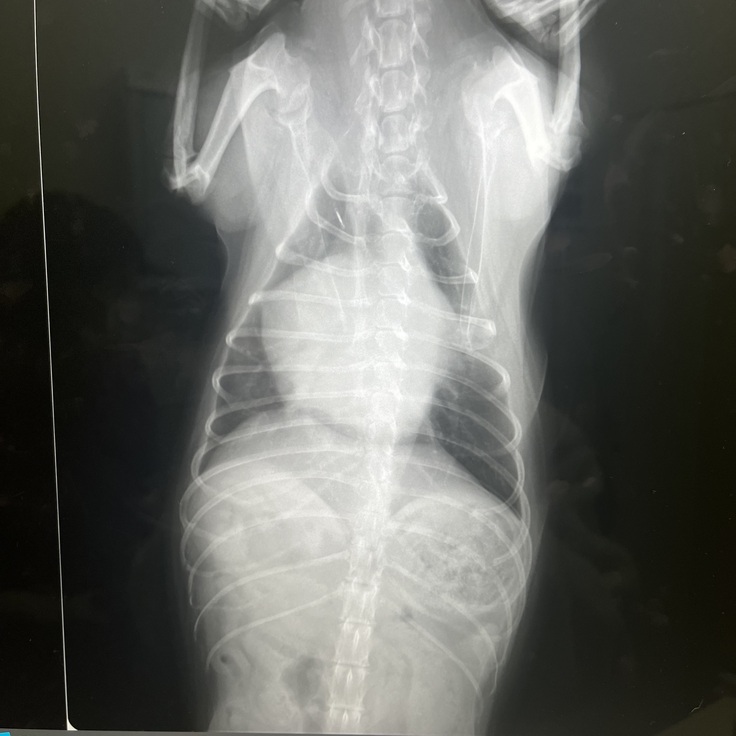

現在のレディの心臓の状態です

健康の犬の心臓に比べパンパンに

膨れ上がった心臓です。

緊急入院した時先生に心臓肥大が酷い、そのせいで気道も圧迫され呼吸数もできずそれに加え肺水腫になっているので相当苦しいはず、